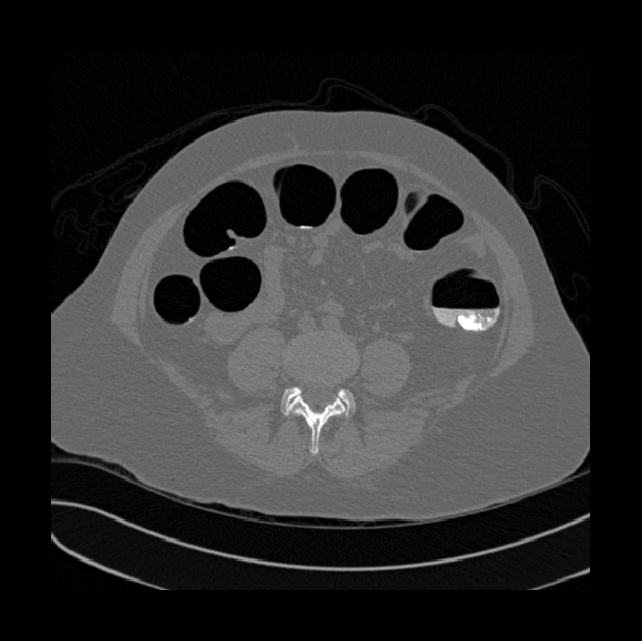

Spinal imaging via computed tomography (CT), magnetic resonance imaging (MRI), radiography, ultrasound, positron emission tomography (PET), and other radiologic imaging modalities is essential for noninvasively visualizing and assessing spinal pathology. Computational methods support and enhance a physician’s ability to utilize these imaging techniques for diagnosis, noninvasive treatment, and intervention in clinical practice. Analysis algorithms developed in the field of computer vision, computer graphics, signal processing, and machine learning have been adapted to analyze spinal images (Li et al., 2015). Conventionally, CT is preferred to study the spine due to a high bone-soft tissue contrast. There are diverse image appearance variations due to differences in vertebral position, metal artifacts and spinal diseases, etc., challenging the analysis algorithms. Fig. 1 gives some examples of these various conditions.

COLONOG. This sub-dataset comes from COLONOGRAPHY dataset related to a CT colonography trial (Johnson et al., 2008). We randomly select one of the two positions (we will open source the codes used for selection), which have similar information for each patient in our dataset. There are 825 CT scans, and they are in a Digital Imaging and Communication in Medicine (DICOM) format.

We calculate the two metrics of each vertebra, and the results are reported in Table 2. On the one hand, our experimental results are close to those reported in reference (Sekuboyina et al., 2020) with the same model (nnUnet), verifying the high quality of our annotations. On the other hand, Table 2 shows it is difficult to segment the diseased vertebrae (the DSC of L6 is almost 0). Specifically, the existence of L6 confuses the model, resulting in prediction dislocations (see the last row in Fig. 4). Thus, our labeled dataset, which contains many L6 cases, is very valuable for the diseased vertebrae segmentation (we have stated those cases that are hard for annotation in the readme.txt file). Table 2 illustrates that the model trained with our annotations can achieve good performance on our CTSpine1K dataset but a much worse performance on the VerSe Challenge datasets, which explains there is an obvious domain gap between our annotated dataset and the public dataset. We infer the reason is that the COlONOG dataset is based on an empty stomach and colon, confusing the deep learning model by the changes of air content in the abdomen (see Fig. 3). Therefore, our annotations are a good complement to the existing datasets.